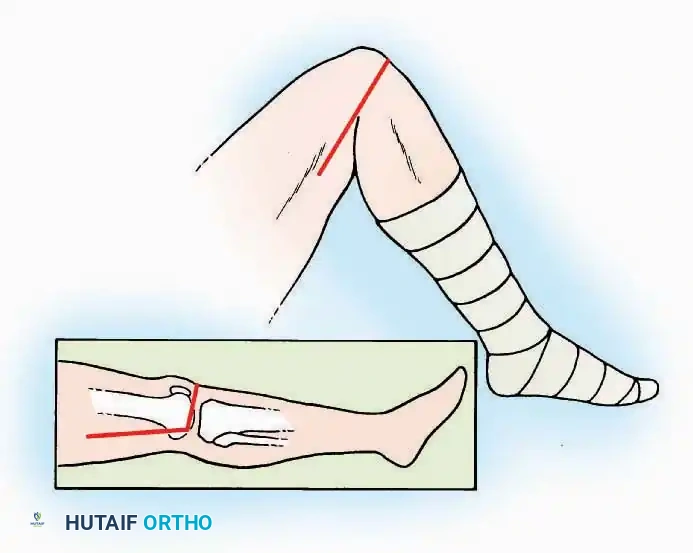

SURGICAL APPROACHES TO THE TOES

Pathologies of the forefoot, including hallux valgus, rigidus, and lesser toe deformities (hammer, claw, and mallet toes), require precise surgical exposures that respect the delicate dorsal and plantar neurovascular bundles.

Approaches to the Interphalangeal (IP) Joints

Indications: Arthrodesis for hammer toe deformities, excision of intra-articular osteophytes, or reduction of irreducible dislocations.

Surgical Technique:

* Great Toe: Make a 2.5 cm longitudinal incision strictly on the medial midaxial aspect of the toe.

* Fifth Toe: Utilize a lateral midaxial incision to avoid interdigital maceration.

* Lesser Toes (2nd, 3rd, 4th): Approach the IP joints through a dorsal longitudinal incision placed just lateral to the corresponding extensor digitorum longus (EDL) tendon.

* Deep Dissection: Carry the dissection sharply through the subcutaneous tissue and superficial fascia directly to the joint capsule.

* Neurovascular Protection: Reflect the skin edges with meticulous care. Retract the dorsal digital nerves and vessels dorsally, and the plantar nerves and vessels plantarward.

* Capsulotomy: Open the capsule either transversely (for joint resection/arthrodesis) or longitudinally (for exploration), exposing the articular surfaces.